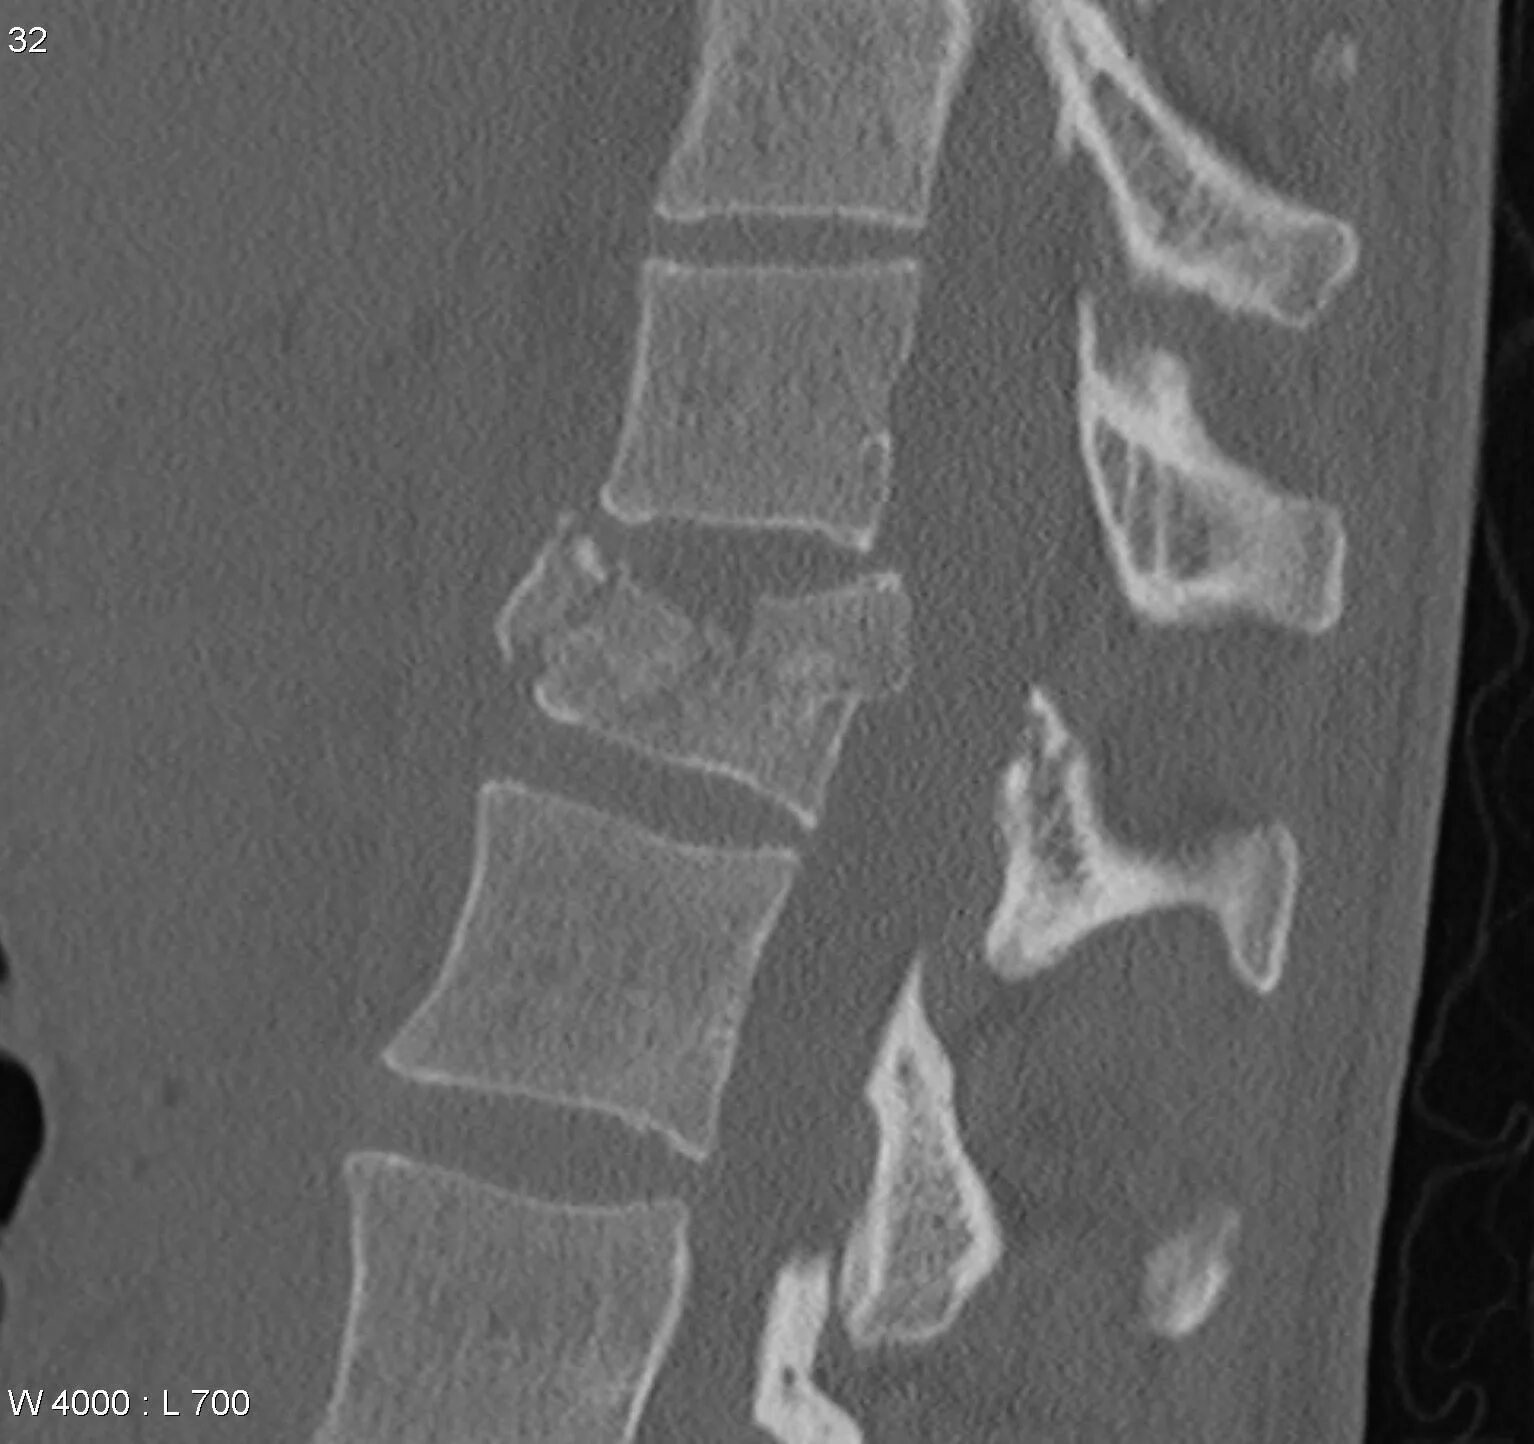

Компрессионно оскольчатый перелом позвонка